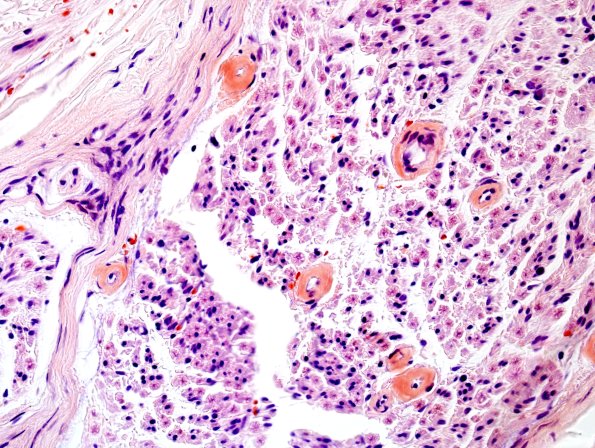

4C1A,B Congo red special stain for amyloid is positive in endoneurial capillaries and venules (4C1A) and demonstrates apple green birefringence under polarized light (4C1B). There is no evidence of vasculitis or inflammation.